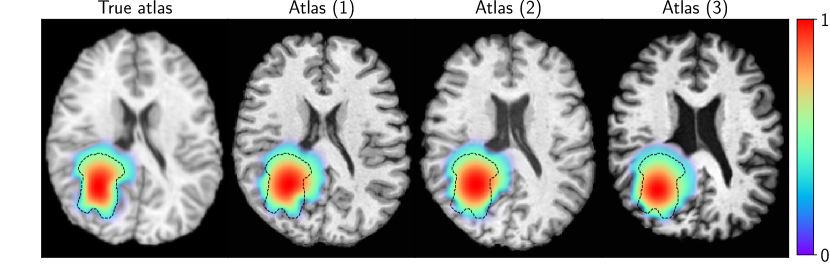

where represents the non-dimensionalized ground truth parameters. The tumors along with the deformed atlas are visualized in Fig. 1. We report our inversion results in Tab. 1 (“True IC”) with tumor initial condition and precancer scan taken as the ground truth. We report the relative errors in reconstructing parameters ι={κ,ρ,γ}𝜄𝜅𝜌𝛾\iota=\{\kappa,\rho,\gamma\} (if the ground truth is zero, then the error is absolute; TC(a)), relative error in the two-norm of the displacement norm u𝑢u, i.e., 𝒖2subscriptnorm𝒖2\|\boldsymbol{u}\|_{2} (this field informs us of the extent of mass effect), relative error in the final tumor reconstruction, and the norm of the gradient to indicate convergence. We observe excellent reconstruction with relative errors less than 2%.

Refer to caption

Figure 1: Synthetic patient T1 MRIs generated with Eq. (1). The normalized tumor concentration is overlaid (color) along with the undeformed ventricles (black dashed contour) to indicate the variable extent of mass effect.

(Q3) Unknown m0subscript𝑚0\boldsymbol{m}_{0}, unknown p𝑝\boldsymbol{p}: This scenario corresponds to the actual clinical problem. For this test-case, we invoke (S.2) and average the results using three atlases. To reiterate the scheme, the inverted tumor ICs from (S.1) are warped to each atlas (through registration) for the final inversion (S.3). We report inversion results in Tab. 2 and show an exemplary reconstruction of the patient using the different atlases in Fig. 2. Despite the approximation error in 𝒎0subscript𝒎0\boldsymbol{m}_{0}, we are still able to capture the parameters (average displacement relative errors of around 16% and 25% for atlases (1) and (2) respectively). Atlas (3) has poor performance because it is significantly different from the patient (for example, the ventricles are highly dissimilar). We also note that the error in tumor reconstruction is significantly higher, which is representative of the errors introduced due to the anatomical variations of each atlas from the patient.

Figure 2: Reconstruction of the tumor concentration (color) using different atlases as the precancer scan. The tumor data segmentation is highlighted as a black dashed contour line.